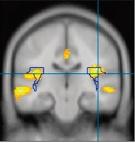

Ainsi, des chercheurs ont montré que certains anticancéreux chimiques empêchent la formation de nouvelles cellules dans l’hippocampe, ce qui perturbe les fonctions cognitives associées à cette région cérébrale, comme la mémorisation et les apprentissages Mais d’autres parties du cerveau seraient aussi touchées Grâce à l’imagerie cérébrale, on a pu constater dans certains cas une diminution de la quantité de matière grise dans plusieurs zones comme le cortex frontal et temporal, le cervelet ou le thalamus, à la suite d’une chimiothérapie La matière grise concentre les corps cellulaires des neurones, c’est-à-dire leur partie centrale, où se trouve le noyau contenant les chromosomes ainsi que les principaux éléments vitaux , alors que la matière blanche désigne les prolongements appelés « axones » qui conduisent l’influx nerveux… Par la suite, en 2013, l’équipe d’Andrew Saykin, de l’école de médecine de l’université de l’Indiana à Indianapolis, aux États-Unis, a scanné le cerveau de 55 femmes atteintes d’un cancer du sein, dont la moitié avait suivi une chimiothérapie un mois auparavant, ainsi que de 24 personnes non malades. Chez les sujets ayant subi une chimio, elle a constaté que le cortex frontal avait diminué de volume par rapport à son état initial d’avant la chimiothérapie Ces personnes se plaignaient de troubles de la mémoire à court

L’effet d’une chimiothérapie sur le cerveau est visible en imagerie par résonance magnétique. Ici, trois vues montrant la moyenne des images obtenues chez 16 patientes de 60 ans et plus traitées pour un cancer du sein, par comparaison avec celles de 15 femmes du même âge en bonne santé. Les régions touchées sont en couleur : plus celle-ci tend vers le jaune pâle, plus la densité de matière grise est faible par rapport au groupe contrôle.

terme ou de la capacité à planifier des actions – deux fonctions exécutives, donc…